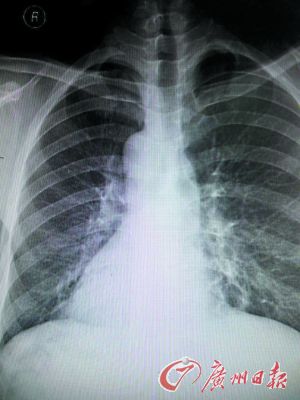

X光片上患者的心臟陰影在右邊。

東莞現鏡面人,五臟六腑長的位置和一般人相反,正常人的心臟、脾臟在左側,肝臟在右側。但日前,東莞市第八人民醫院收治的一名病人正好相反,他的心臟、脾臟在右邊,肝臟在左邊。

醫生趕快拿起聽診器聽診心音區,發現患者右側心音較左側明顯,跟常人相反。經胸片、心電圖及B超等檢查后,確診患者為急性化膿性闌尾炎內臟反位,也就是“鏡面人”得了闌尾炎。